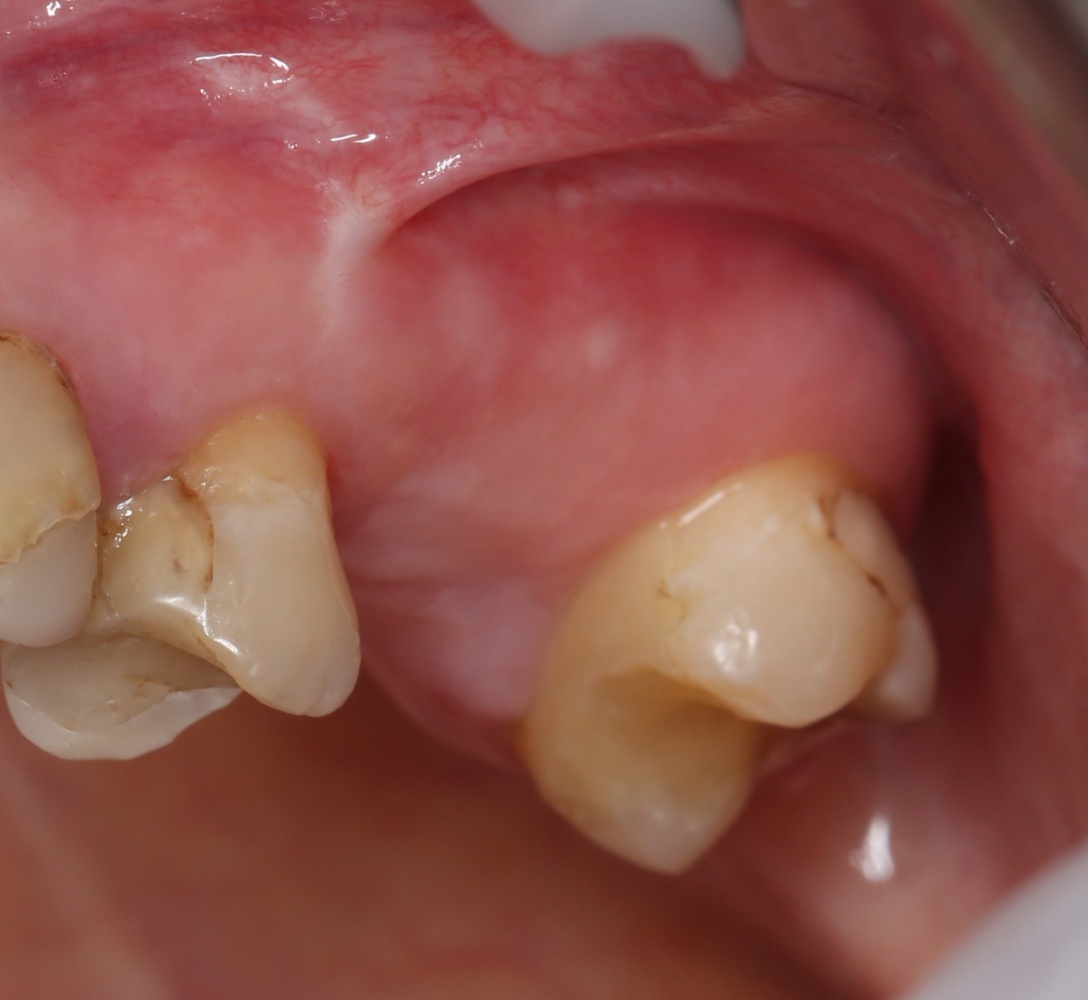

Вот клиническая картина через 4 месяца после ранее проведенной имплантации с остеопластикой:

Как видишь, коллеги из недалекой дружественной страны не осилили снятие швов. Мне это не нравится, хотя и объясняет, почему люди готовы ехать за тыщи километров ради 20-минутной операции удаления зуба мудрости.

Ну хорошо. Швы сняли. Делаем разрез. Обрати внимание, что после всех проведенных операций у нас остается очень небольшой по ширине слой жевательной слизистой оболочки: